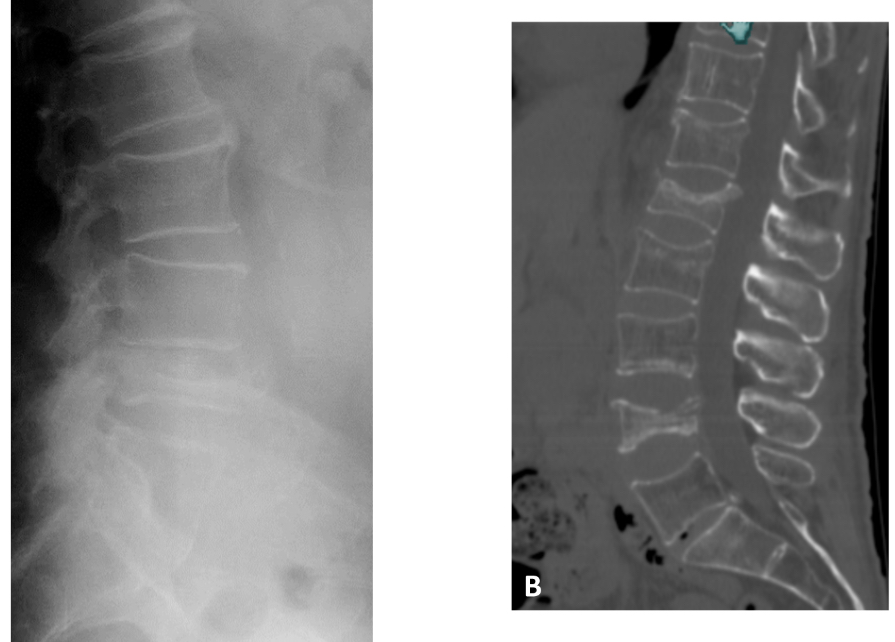

Discopathie dégénérative L5-S1

pincement discal

Ostéophytes antérieurs